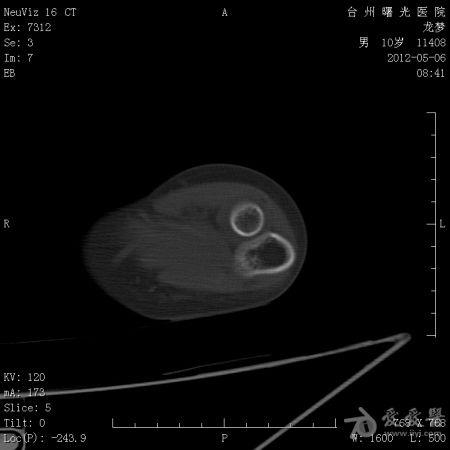

年龄:10岁主诉: 右上臂疼痛活动受限20余天现病史: 20余天前摔伤致右肘部疼痛活动不利,曾在外院治疗,X线:右肘部未见明显异常。肘关节活动尚可,于活血化瘀,消肿止痛治疗。20余天疼痛未见明显好转,肘关节活动不利,***就诊。既往史: 既往健康

体格检查: 一般状况好,发育良好,营养中等。头颅五官胸腹未见异常。右肘部,右上臂下端肿胀,压痛、纵向叩击痛(+),局部肤温增高。肘关节固定于约40°,背伸约20°,肘屈约100°,表面无血管充盈,无色素沉着。右上肢皮肤感觉正常,右桡动脉搏动正常。

初步诊断: 左肱骨下端骨肿瘤X线检查显示左肱骨中上段有虫蚀样 低密度改变,局部硬化,可见骨膜反应,病理性骨折鉴别诊断: 动脉瘤样骨囊肿,骨结核诊疗过程:

讨论内容:患者病史极短,摔伤后检查未见明显异常,初次就诊,复诊时间间隔约16天,未留下初次就诊的X线资料,仅感觉肱骨下端较上段骨密度稍减低。

骨肉瘤多见于小儿,多发生于干骨端,常见于股骨远端和胫骨近端。骨肉瘤的X线表现:⒈骨质破坏⒉肿瘤骨⒊肿瘤软骨钙化⒋软组织肿块⒌骨膜反应和Codman三角。动脉瘤样骨囊肿多发生于10-20岁,可发生生于长骨和脊柱。动脉瘤样骨囊肿的X线表现为长骨干骺端的溶骨性、偏心性骨破坏,其偏心向外突出如气球状膨胀,病变呈局限性透亮区,边界清楚,边缘有狭窄的硬化带,其中有不规则的分隔,呈蜂窝状。位于骨中心者,向周围扩张膨胀,呈卵圆形,与骨的纵轴一致。囊肿表面有一薄的骨壳,可有一层薄的骨膜反应。位于脊椎的病变多在脊突、椎板、横突上,亦可膨出于骨外。 根据以上特点和本病例的表现,骨肉瘤可疑。